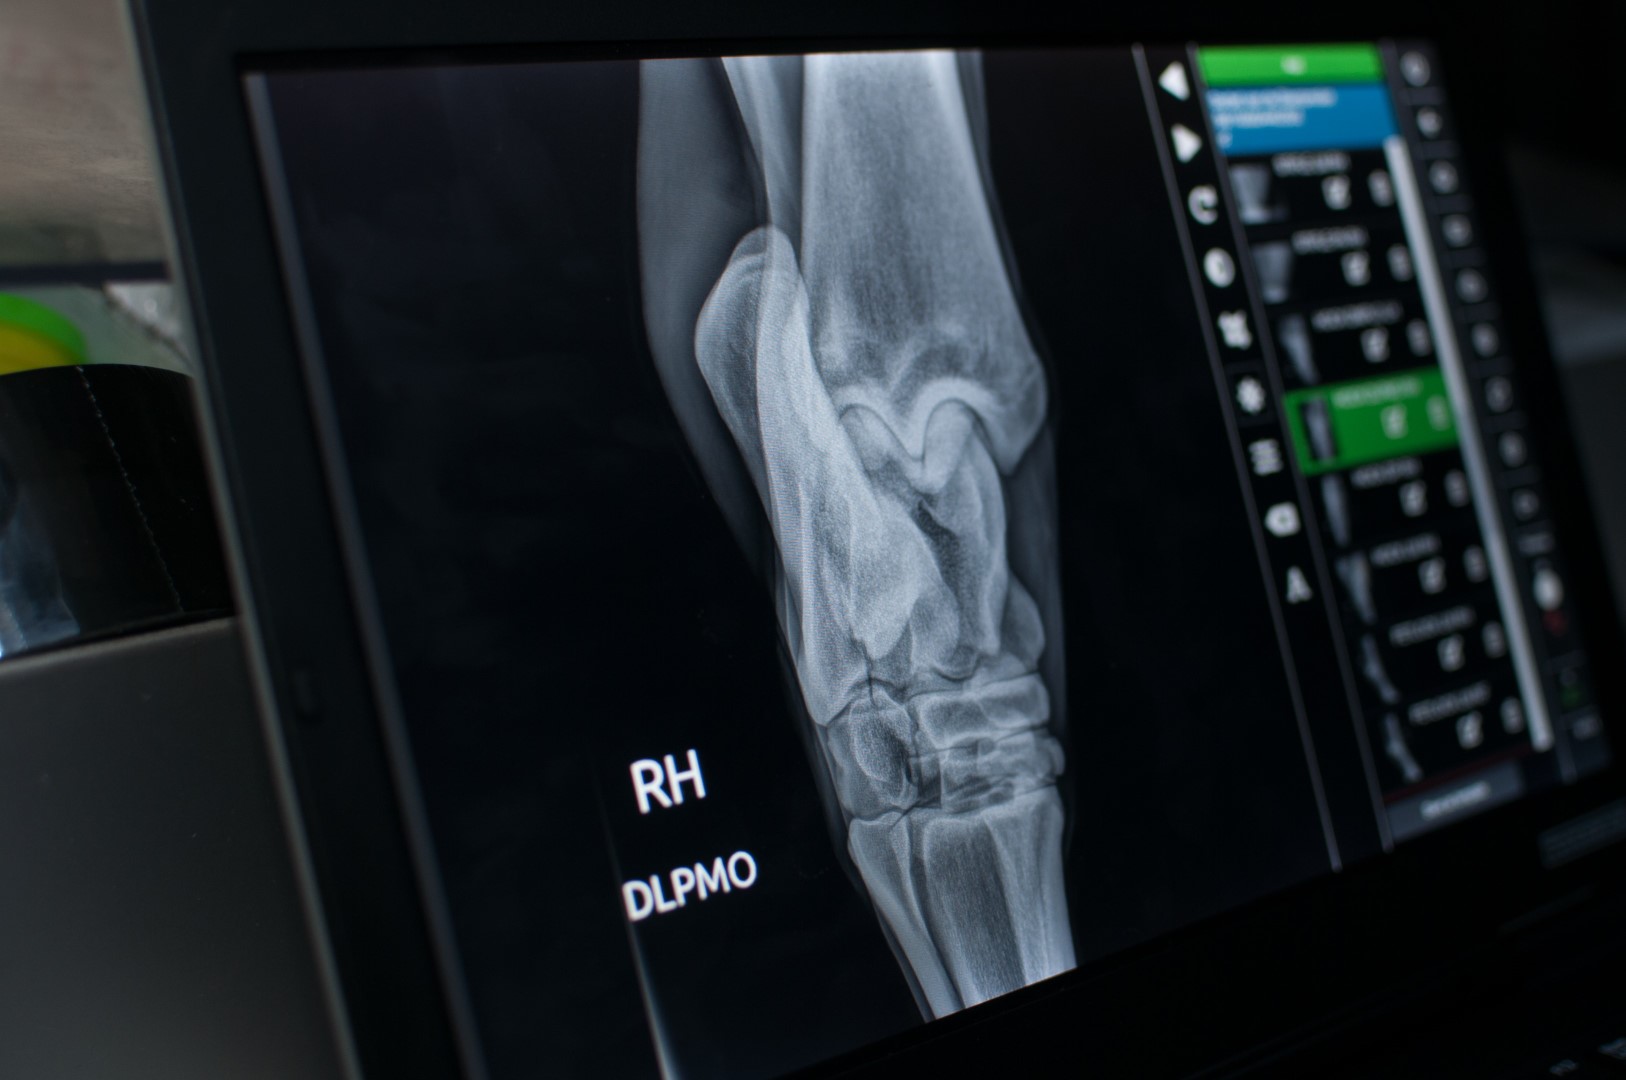

Problemen van het bewegingsstelsel uiten zich meestal door manken. Een correct mankheidsonderzoek bestaat uit een grondig klinisch onderzoek met inspectie, palpatie en een bewegingsonderzoek, al dan niet aangevuld met diagnostische lokale verdovingen. Om een adequate behandeling en een volledige diagnose te stellen, wordt er vaak gebruik gemaakt van gepaste beeldvormingstechnieken (radiografie en echografie). Aan de hand hiervan wordt er een behandelingsschema opgesteld, gevolgd door aangepast trainingsschema om uw paard zo snel mogelijk op het juiste pad te helpen.

Waar nodig wordt er samen met de hoefsmid overlegd om een beslagaanpassing door te voeren.

Verder vallen nog onder orthopedie:

Voordat een jong paard in het werk komt, is het altijd aangeraden om een radiografische keuring te laten uitvoeren. Bij deze screening kunnen erfelijke en ontwikkelingsgerelatereede problemen worden opgespoord zoals Osteochrondose dissecans (OCD of “Chip), Cystes,...

Volledige radiografische screenings kunnen uitgevoerd worden vanaf de leeftijd van 18 maand. De standaardkeuring bestaat uit 18 foto's waarbij de meest frequente aandoeningen van de ledematen kunnen opgespoord worden. Voor een uitgebreider pakket kunnen altijd bijkomende opnamen besproken worden.